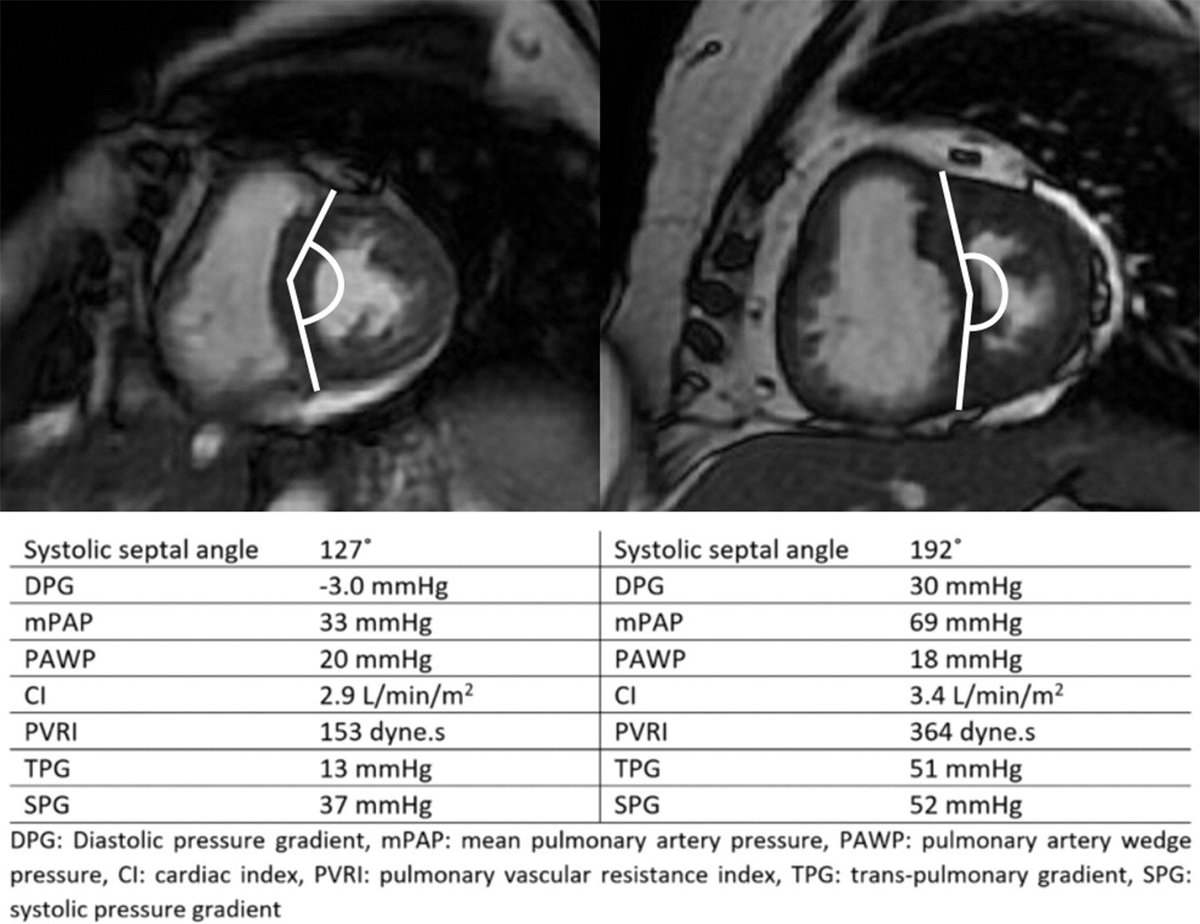

Johns et al assess interventricular septal angle in identification of combined per- and postcapilary pulmonary hypertension in patients with pulmonary hypertension due to left heart disease. http://ow.ly/XfLp30kPLi4 pic.twitter.com/NmmCIR523j